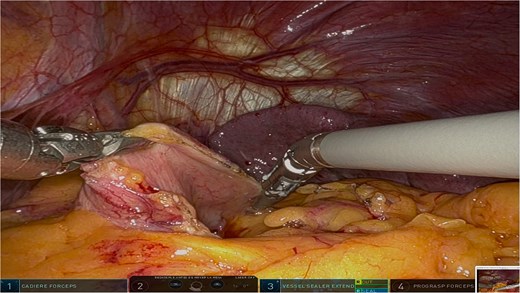

The surgery was performed using the Da Vinci robotic system under general anesthesia. The patient was positioned supine with reverse Trendelenburg. Four robotic trocars and one assistant trocar were placed. The gastro-splenic ligament was dissected to expose the distal pancreas, and the pancreas was transected using a linear stapler, ensuring tumor-free margins (Fig. 2). The splenic artery and vein were individually ligated with robotic sutures, and the spleen was mobilized and removed along with the pancreas (Fig. 3). The specimen was extracted via mini-laparotomy and sent for histopathological analysis (Fig. 4).

Intraoperative image highlighting the robotic ligation of the splenic artery. The Da Vinci system facilitated precise dissection and secure vascular control, minimizing blood loss and ensuring the preservation of adjacent structures, such as the splenic vein. This step was critical for the safe resection of the distal pancreas and spleen.